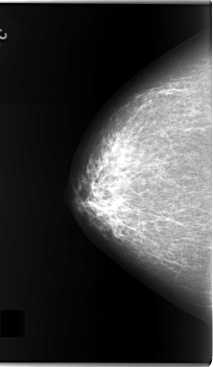

C_0124_1.RIGHT_MLO

RIGHT_CC LINES 5872 PIXELS_PER_LINE 3408 BITS_PER_PIXEL 12 RESOLUTION 50 NON_OVERLAY

RIGHT_MLO LINES 5952 PIXELS_PER_LINE 3624 BITS_PER_PIXEL 12 RESOLUTION 50 NON_OVERLAY